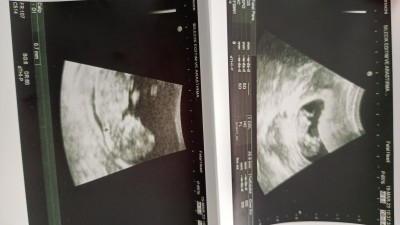

İlk bebişim kizlar 11+4 gunluk sizce cinsiyet tahmini alabilir miyim deneyimlerinizden

image